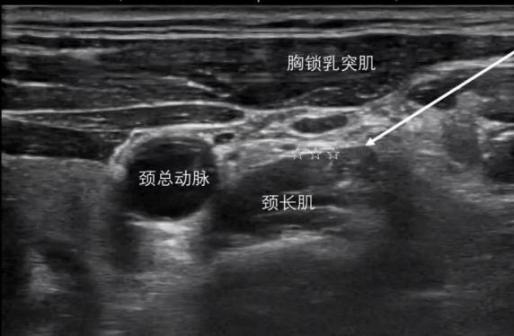

根據每位患者的具體情況,采用多樣化的治療方法,包括睡眠監(jiān)測、人工壓力滴定、認知行為療法、星狀神經節(jié)阻滯、中醫(yī)治療等,幫助患者擺脫藥物依賴,建立無藥睡眠。

星狀神經節(jié)阻滯 行為認知療法